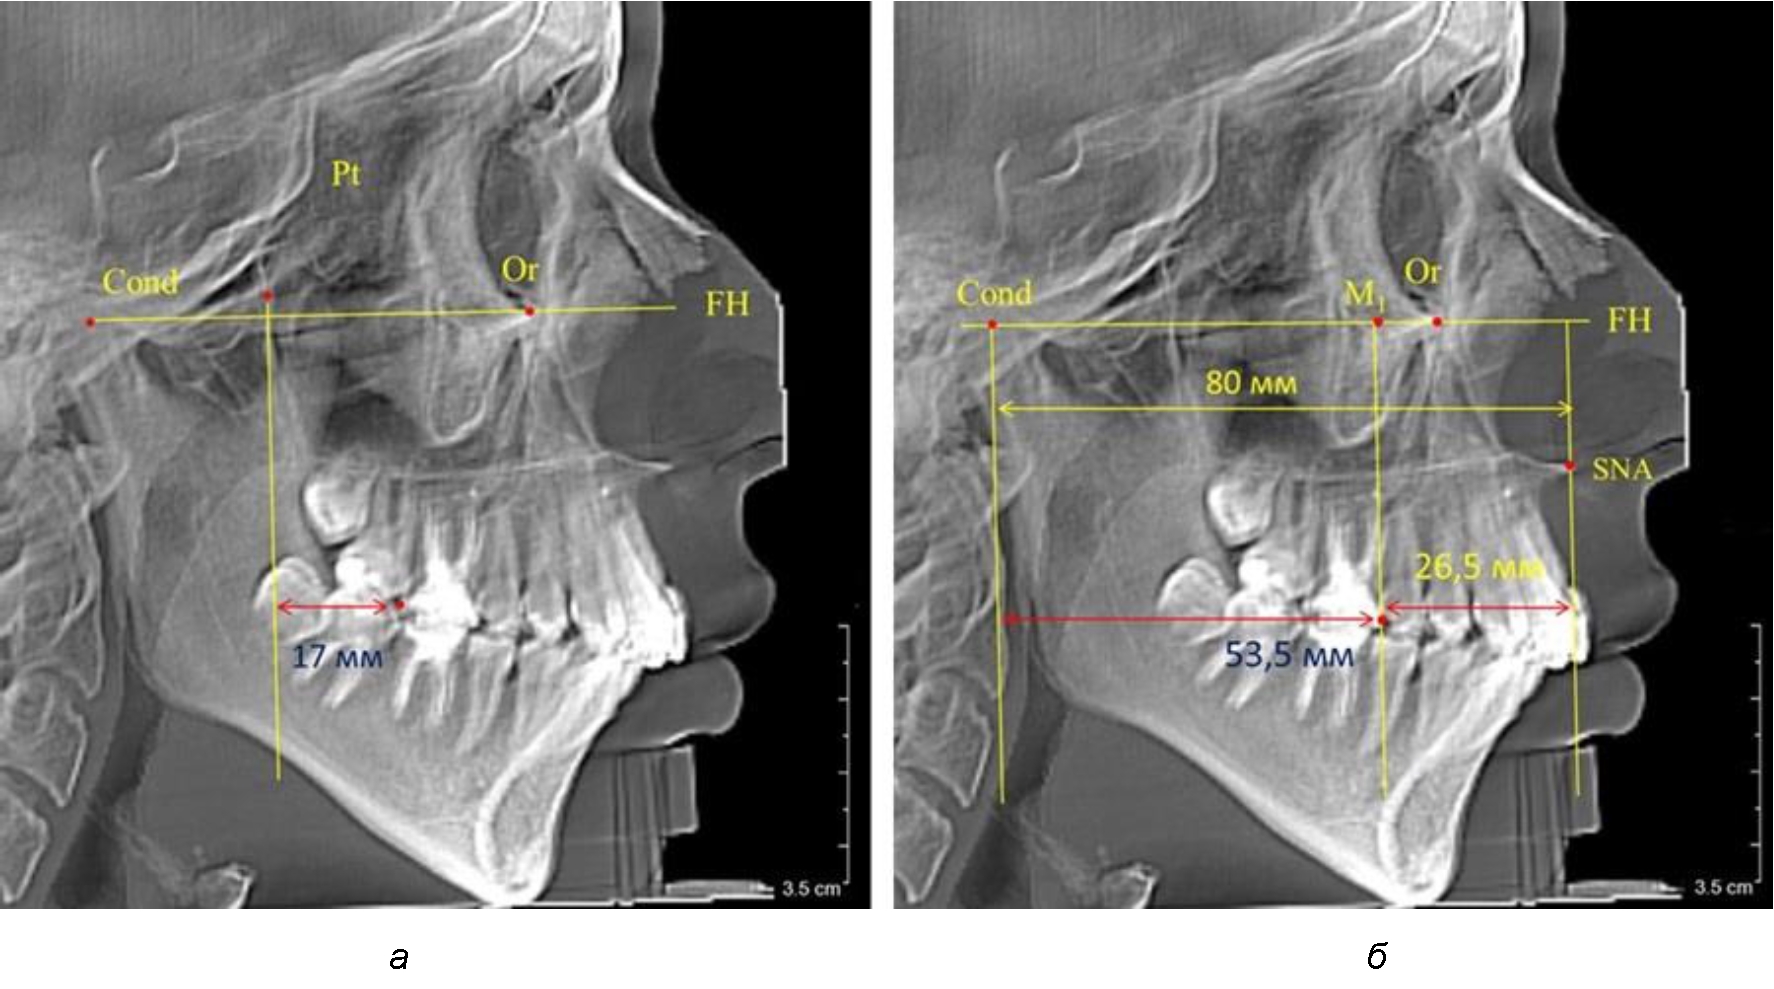

Рис. 4. Особенности положения первых моляров по R. E. McDonald (а) и по предложенному методу (б) у ребенка 4 лет

Рис. 5. Особенности положения первых моляров по R. E. McDonald (а) и по предложенному методу (б) у ребенка 8 лет

Второй частью исследования был анализ положения первых постоянных моляров в различные периоды сменного прикуса. На телерентгенограммах детей периода прикуса молочных зубов дистальная поверхность зачатка первого постоянного моляра отстояла от крыловидной вертикали на величину, составляющую около 7 мм, что было близким по значению к данным R. E. McDonald. Сагиттальный размер гантического отдела составлял около 60 мм, а его отношение к кондилярно-молярной глубине – 1,5 (рис. 4).

По мере роста челюстей увеличивалась глубина гнатического отдела лица, и кондиллярно-спинальный размер составлял в среднем (74,57 ± 0,93) мм. Дистальная поверхность первого постоянного моляра отстояла от крыловидной вертикали на величину, составляющую около 11 мм, что, так же, как и в периоде прикуса молочных зубов, было близким по значению к данным R. E. McDonald, а именно возраст, плюс 3 мм. Однако величина ошибки среднего значения свидетельствовала о вариабельности признака даже в восьмилетнем возрасте после замены передней группы зубов и установки ключевых постоянных моляров в окклюзионное равновесие. Обращает на себя внимание отношение глубины гнатического отдела лица к дистальному отделу, а именно к кондилярно-молярному расстоянию (рис. 5).